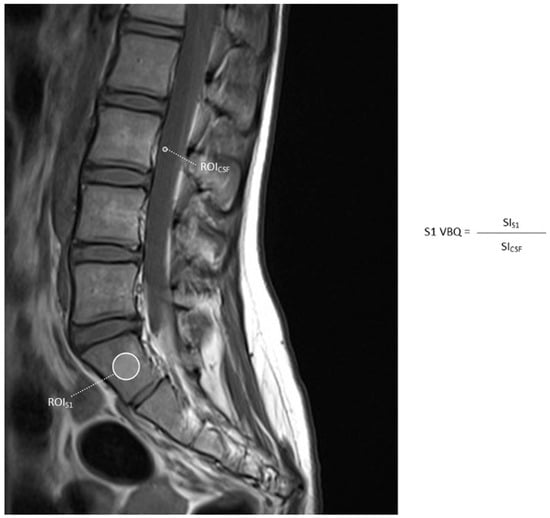

3.3. S1 VBQ